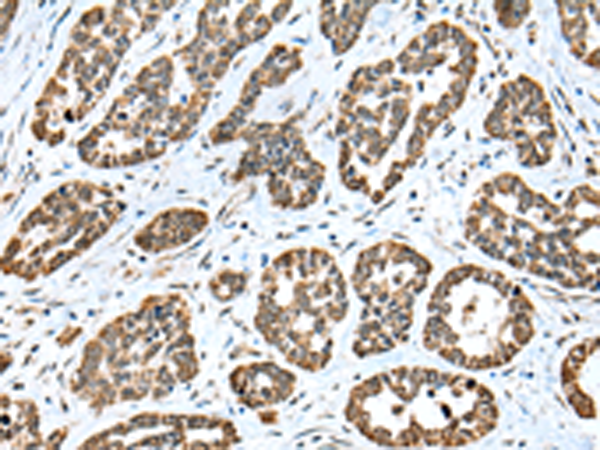

分类: 科研抗体货号: P02193别名: PX19; PRELI; SBBI12; CGI-106应用: IHC反应种属: Human, Mouse